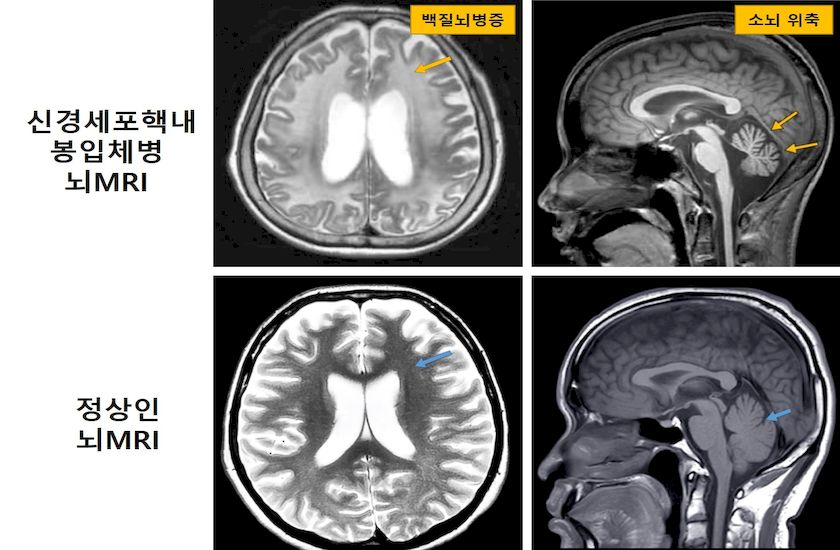

‘신경세포핵내봉입체병’은 비정상적인 단백질(봉입체)이 축적되는 신경퇴행성장애다. 원인은 NOTCH2NLC 유전자에서 GGC 염기서열이 비정상적으로 반복되는 ‘단연쇄반복 변이’ 때문이다.

주로 성인기 발병하며 백질뇌병증, 진행성 인지기능 장애, 실조증과 같은 다양한 신경학적 증상을 동반한다.

이를 활용해 서울대병원에 내원한 원인불명 백질뇌병증 환자 90명 중 신경세포핵내봉입체병 영상 소견이 있는 환자의 전장유전체 데이터 분석이 이뤄졌다.